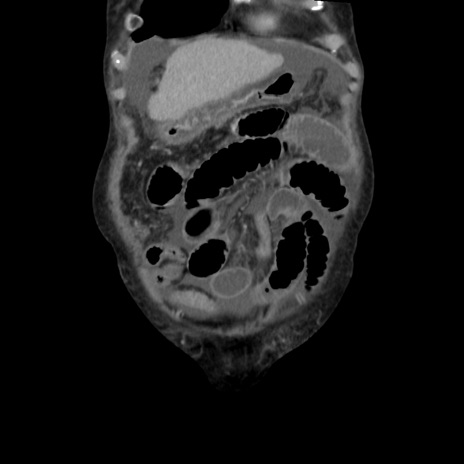

症例31(冠状断像)

【症例】80歳代 女性

【主訴】腹部膨満感

【現病歴】他院にて肝硬変にてフォロー中。1週間前から便秘、腹部膨満感、臍部腫瘤あり受診となる。

【既往歴】肝硬変

【身体所見】腹部膨隆あり、皮膚変化なし、疼痛なし。

【データ】WBC 4600、CRP 0.25